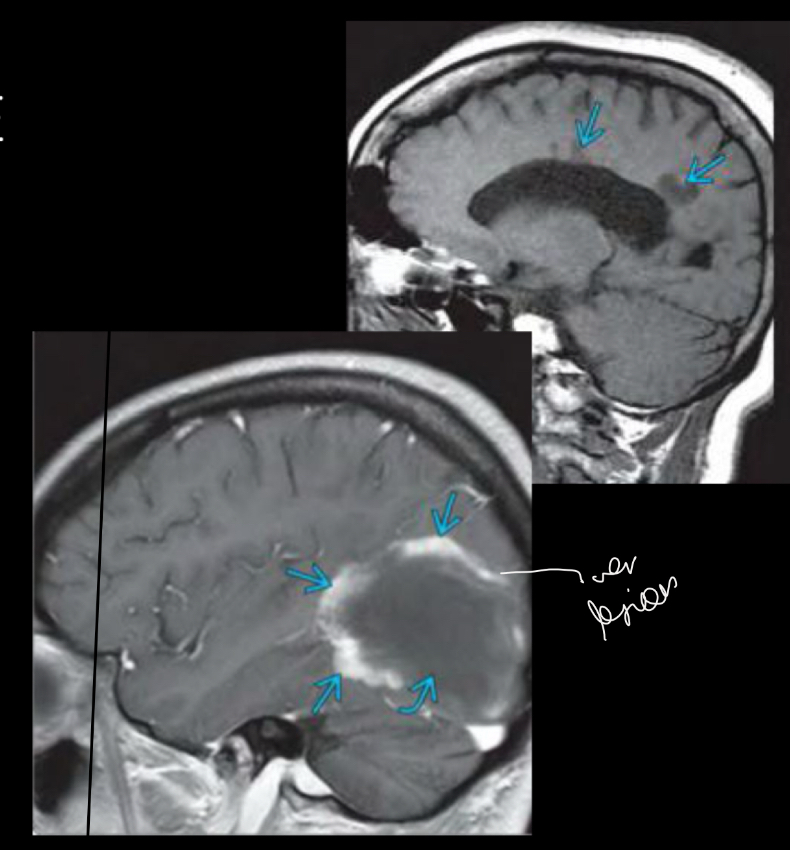

q ves en imagen

A

hiperintensidades calloseptales en T2 Y FLAIR

Peque, lineales, ovoide

Periventriculares

Dedos dawson

en q plano ves DEDOS DAWSON EXAMEN

Plano sagital

Dedos de dawson se ven